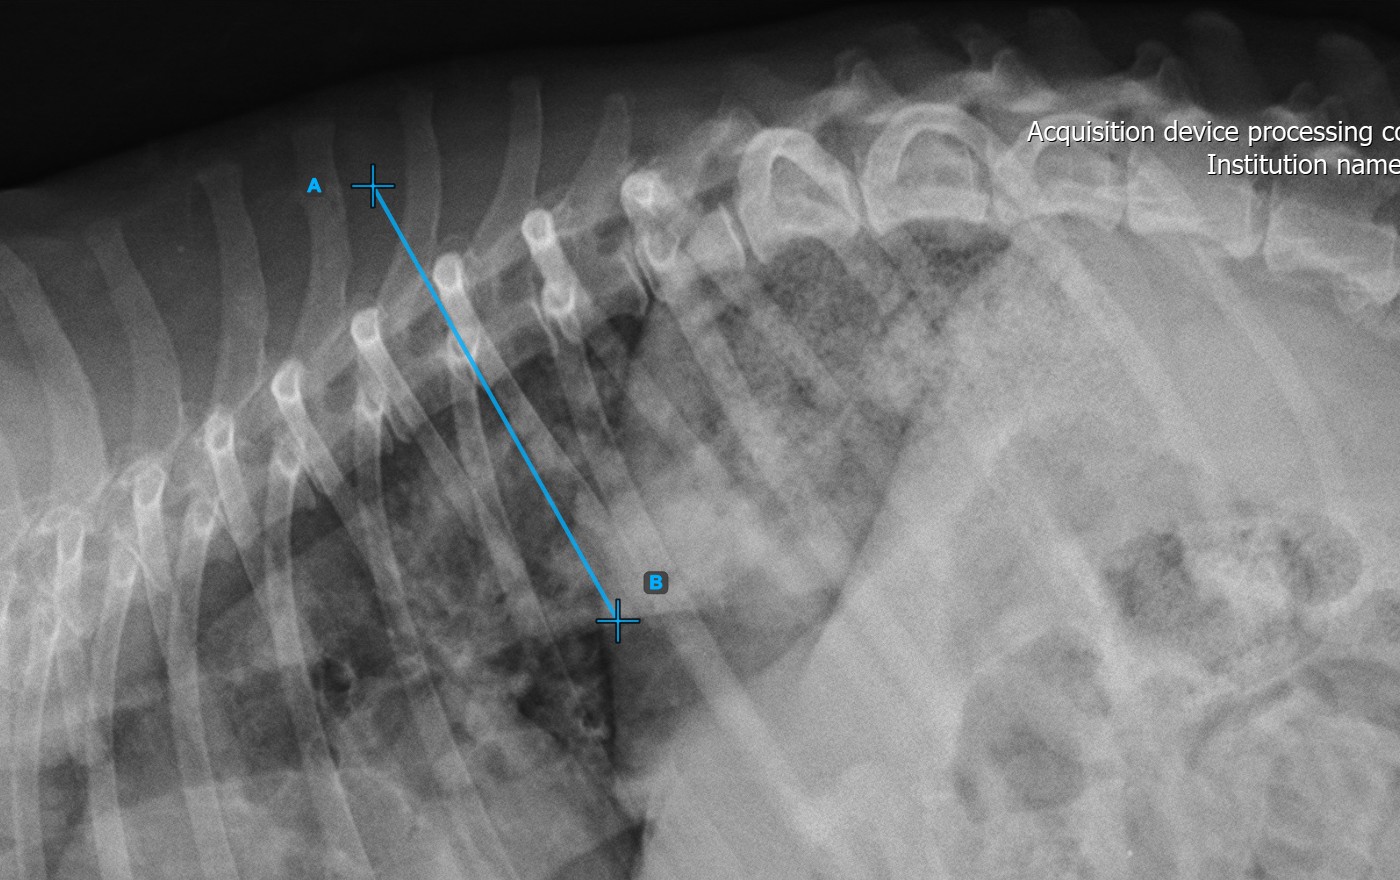

The image below represents a typical placement of the first vertebral line.

Mark the second vertebral line on the spine to calculate the deformity.

Identify the vertebral endplate at the opposite end of the largest spinal curve deformity. Place the start and end point of the second vertebral line precisely along the identified endplate. Adjust each point on the scene to better align the line with the endplate if needed.

The image below represents a typical placement of the second vertebral line.